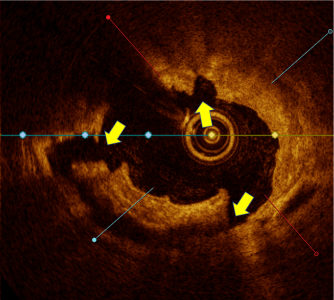

OCT Imaging Confirmed High Fracture Depth and Width Even in Complex Calcified Lesions

Calcium score 4

EXR_Clinical-Evidence_Calcium-Score-4_1.png

EXR_Clinical-Evidence_Calcium-Score-4_2.png

OCT analysis demonstrated effectiveness of the novel mechanism of action (N = 32; L = 32#)

• Calcium fracture and fragmentation was identified in >90% of the calcified lesions with multiple fractures in 75% lesions

• Calcium fracture depth of 0.81mm ± 0.33 and fracture width 0.66mm ± 0.29

• Deep calcium fractures in eccentric and concentric calcified lesions post HC-IVL, confirming the mechanism of action of HC-IVL.